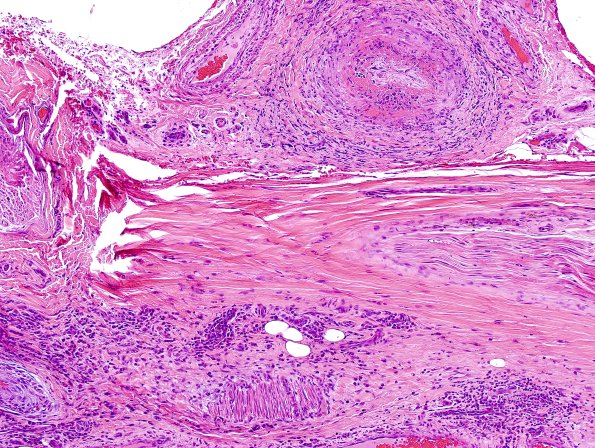

Epineurial vessels often exhibit fibrinoid necrosis which is rare in the endoneurium.